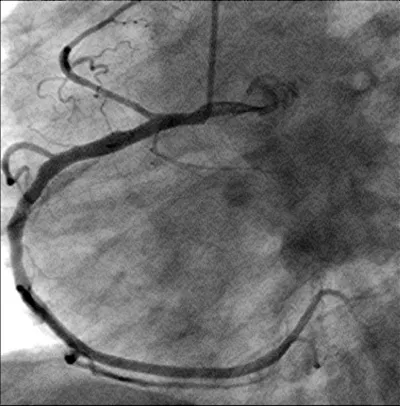

A 56-year-old obese man with a history of hypertension was admitted at night to the department of cardiology of our hospital because he had developed sudden onset right-sided thoracic pain with radiation into the right shoulder and right arm. He was sweating profusely and had massive nausea. The initially performed 12-lead ECG showed marked inferior ST segment elevations (Figure 1). Beside analgetics and oxygen, he was treated with aspirin, clopidogrel, heparin and the fibrin-specific thrombolytic tenecteplase. His symptoms resolved after 30 minutes. However, half an hour later, he developed left-sided thoracic pain, tachycardia, low blood pressure and the ECG signs of anterior ST-segment elevation myocardial infarction. The performed coronary angiography revealed a normal right coronary artery (Figure 2). The left coronary artery showed a long dissection of a large ramus circumflexus (RCX) (Figures 3,4). Additionally, the left anterior descending coronary artery (LAD) was occluded at about the mid-level (Figure 4, asterisk). Afterwards the left ventriculography revealed a reduced function and a Stanford type A aortic dissection with the intimal flap (Figure 5, arrows). Immediate patient transfer for emergency surgical intervention was arranged. During transport, ventricular fibrillation occurred, and he required endotracheal intubation as well as prolonged cardiopulmonary resuscitation. Unfortunately, he died due to a refractory cardiogenic shock during further transport.

Figure 4: The left coronary artery shows an occlusion of the left anterior descending coronary artery (*) (left anterior oblique projection, RCX: ramus circumflexus).